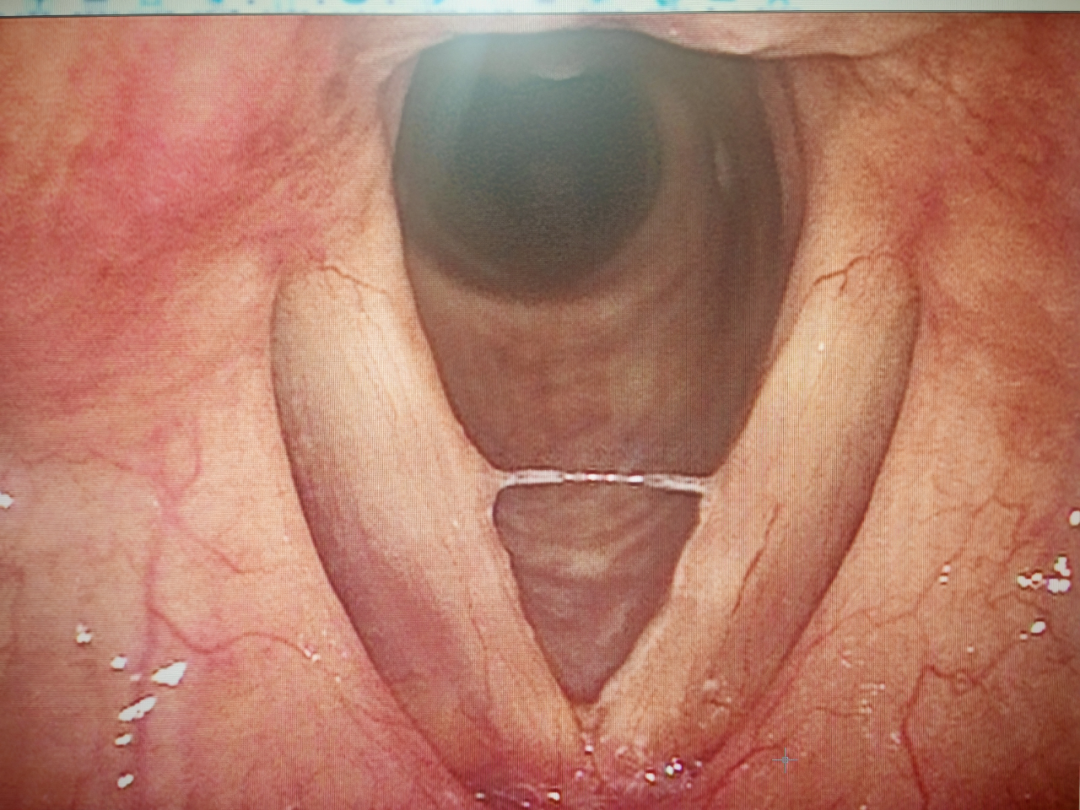

图片

治疗后